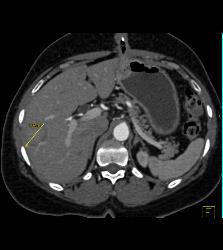

GIST Tumor With Ulceration